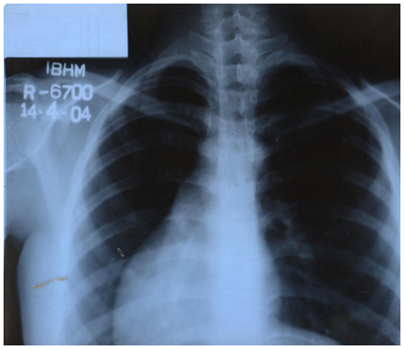

On investigation, her Hb% was10.7gm/dl, Total WBC count was 15,200/cumm, polymormphs was 72%, lymphocytes was 19%. USG showed dextrocardia with situs inversus and right adnexal cyst (simple follicular). After we got this report Echocardiogram was done and comment was heart on right side of the chest, mild concentric LVH with good systolic LV function. After confirmation of the diagnosis of situs inversus totalis, laparoscopic surgery was planned as it can help in confirmation of diagnosis and operation can be done with minimum handling. Three ports one on umbilicus, one on left iliac fossa and third one on suprapubic region slightly to the left were made. Whole abdomen was checked thoroughly. Finally lap.appendicectomy was done. Postoperative recovery was good (Figure 3).

Figure 3 CXR – Mrs Tahera.

Figure 5 CXR - Mrs Morzina.